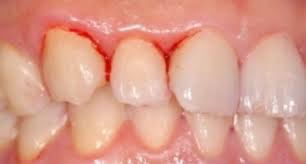

⑧ 잇몸 출혈, 멍, 코피

– 간의 응고 인자 생성 기능 저하로 인해 멍이 쉽게 들거나 잇몸 출혈이 자주 발생할 수 있습니다.